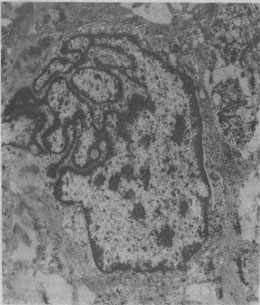

图1-1 恶性肿瘤细胞的奇异形核

图中央为一巨大的瘤细胞核,核膜曲折凹陷,使核呈奇异形(纤维肉瘤的电镜照片)